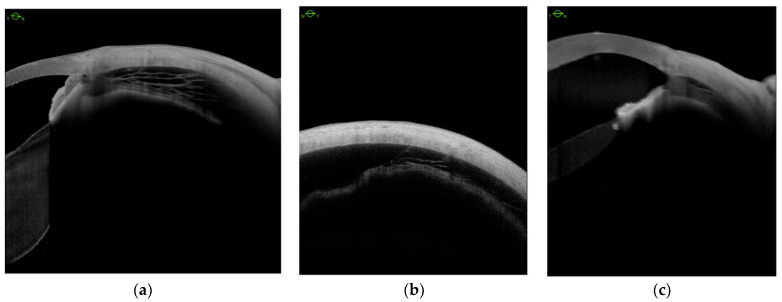

Ciliary body detachment (CBD) secondary to the advanced cyclitic membrane associated with PVR grades C and D was detected in all eyes with hypotony (Table 1). We defined three patterns of CBD: (1) detachment between the longitudinal, circular, and oblique fibers (Figure 2a); (2) complete detachment with supraciliary fluid of varying thicknesses in all 4 quadrants (Figure 2b); (3) detachment in the pars plicata (Figure 2c).

We analyzed CBD before and after scleral buckling surgery (Figure 3a,b), and no eye showed any significant changes postoperatively (Figure 3c,d).